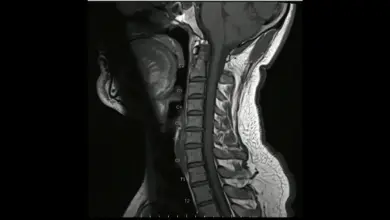

Cirurgia de deformidade cervical: guia completo

A cirurgia de deformidade cervical é indicada para corrigir desvios no alinhamento do pescoço que geram dor, limitação de movimento…